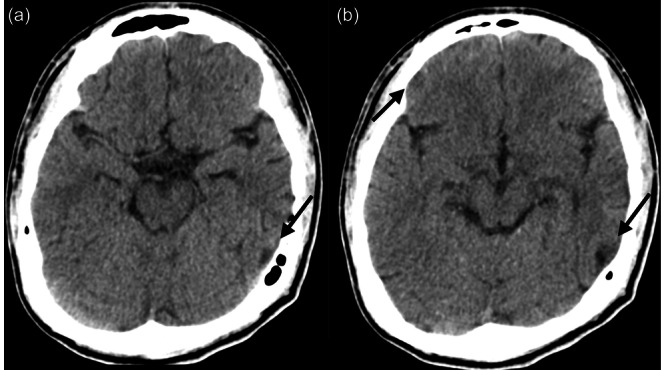

Case presentation: We report the case of a 17-year-old Japanese male who developed OCD after traffic trauma. The patient developed a fear of contamination and checking compulsion after injuring his right OFC and left temporal lobe when he ran into a running truck during a suicide attempt. We believe that the patient's fear of contamination can be diagnosed as true post-TBI OCD. However, his memory impairment was significant, and we considered his checking compulsion to be strongly influenced by cognitive dysfunction due to TBI. We attempted behavioral therapy for OCD; however, sufficient results were not achieved because of the interference from the sequelae of TBI.